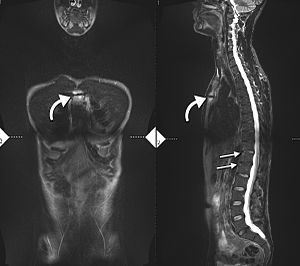

Lateral X-ray of the mid back in ankylosing spondylitis

X-ray showing bamboo spine in a person with ankylosing spondylitis

The earliest changes demonstrable by plain X-ray shows erosions and sclerosis in sacroiliac joints. Progression of the erosions leads to widening of the joint space and bony sclerosis. X-ray spine can reveal squaring of vertebrae with bony spur formation called syndesmophyte. This causes the bamboo spine appearance. A drawback of X-ray diagnosis is the signs and symptoms of AS have usually been established as long as 7–10 years prior to X-ray-evident changes occurring on a plain film X-ray, which means a delay of as long as 10 years before adequate therapies can be introduced.[25]